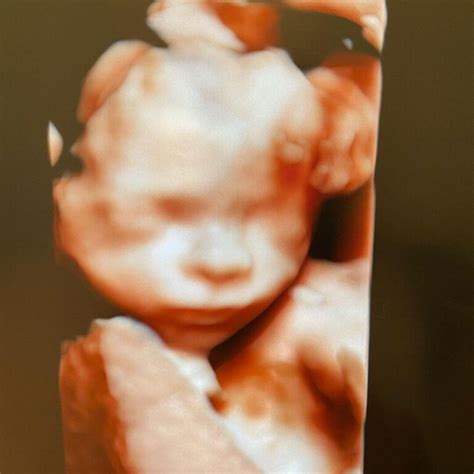

Morfologia fetală realizată în cel de-al doilea trimestru de sarcină permite observarea în timp real a mișcărilor, iar medicul poate realiza reconstrucții 3D și 4D ale fătului. Mai mult, se pot vedea cordonul ombilical și placenta, astfel încât posibilele complicații să fie descoperite din timp.

Îți va fi arătat chipul fătului, mâinile, în acest timp putând fi realizate și fotografii, pentru a fi păstrate ca amintire de către părinți.

Morfologia fetală realizată în cel de-al doilea trimestru de sarcină permite observarea în timp real a mișcărilor, iar medicul poate realiza reconstrucții 3D/4D ale fătului. Mai mult, este posibilă vizualizarea cordonului umbilical și a placentei, astfel încât eventualele complicații să fie descoperite din timp.